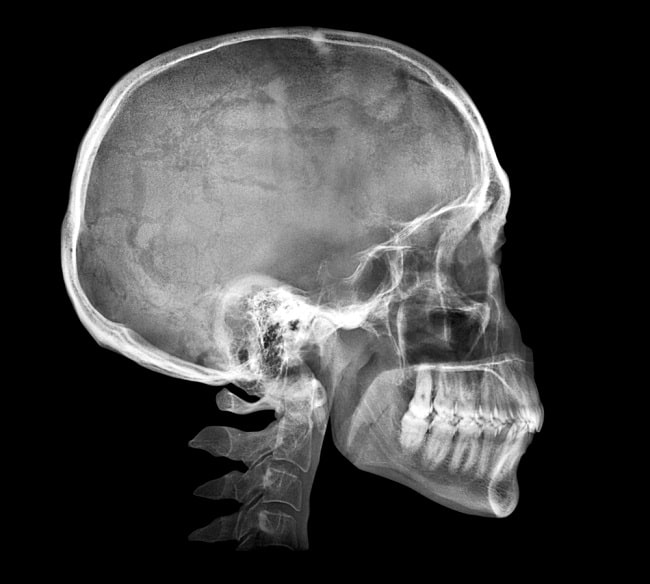

Rontgen kepala adalah prosedur diagnostik yang dilakukan dengan sinar X untuk mengetahui berbagai kelainan di bagian kepala, seperti pada kasus sinusitis, mastoiditis, dan trauma wajah.

Pada praktik klinis saat ini, rontgen kepala sudah mulai ditinggalkan dan digantikan oleh CT scan kepala atau MRI karena lebih sensitif untuk diagnosis lesi tulang dan lebih dapat menyajikan informasi mengenai otak dan jaringan lain. Tetapi, rontgen kepala masih dianggap sebagai pemeriksaan radiologi lini pertama pada pasien yang dicurigai mengalami lesi kranium dan terkadang masih dipakai untuk menentukan arah diagnosis.

Rontgen kepala dapat digunakan untuk mengevaluasi implant surgikal seperti shunt, implan koklea, kateter intratekal, dan deep brain stimulators. Rontgen kepala juga bisa dipakai untuk survei skeletal, misalnya pada kasus kecurigaan penganiayaan anak, displasia skeletal, myeloma multipel, dan penyakit Paget.[1-3]